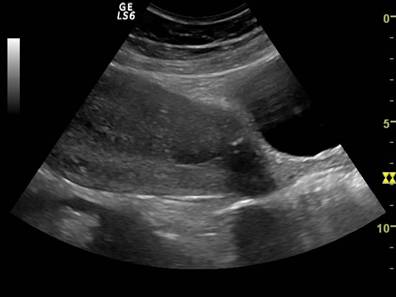

Fig. Nr. 332. Uterul postoperatie cezariana, ziua a IV a